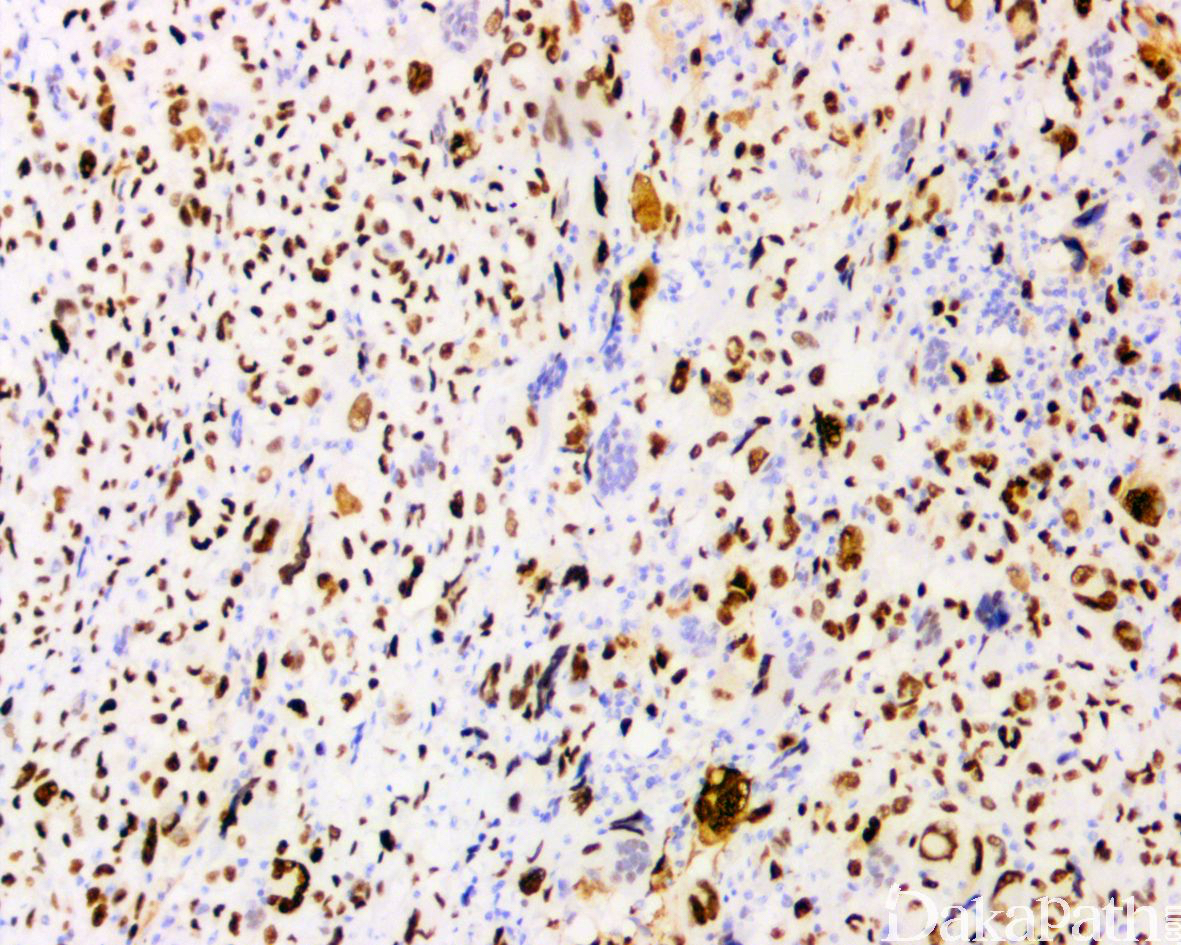

特殊染色和免疫组织化学:vimentin、CD68 阳性;

无特征性标记,vimentin、CD68 阳性;actins、结蛋白和 h-caldesmon 可局灶阳性,偶可表达 CK 和 EMA,少数病例还可局灶表达 S-100,不表达 HMB45,常见 P53 过表达和 Rb1 蛋白表达缺失,其诊断往往是排除性诊断。